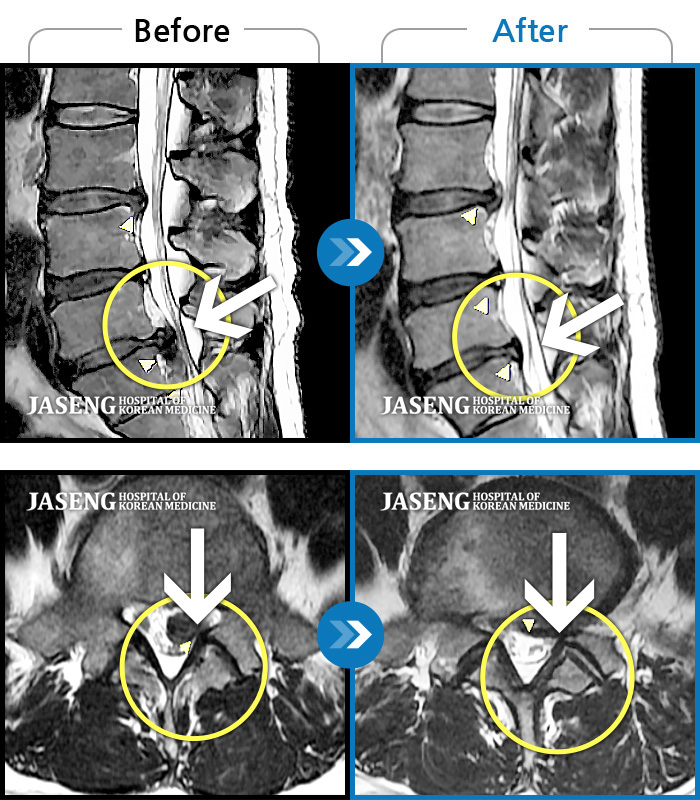

허리디스크

도움받은 사례

해운대 · 김상돈 원장

하지 저림과 통증이 개선되어서 일상생활이 너무 즐겁습니다.

촬영시기

2023.09.18 ~ 2025.01.27

2025.02.05

조회수 16,645